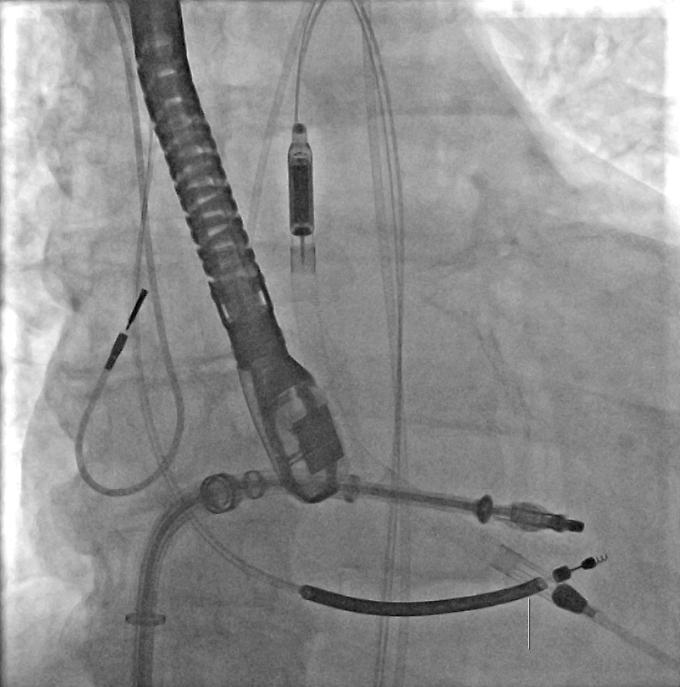

ANDRIA - Un intervento cardiologico mai eseguito prima in Puglia è stato portato a termine con successo all’ospedale “Lorenzo Bonomo” di Andria. Nei giorni scorsi, un paziente di 62 anni è stato sottoposto a una riparazione transcatetere della valvola mitrale con il supporto del sistema di assistenza ventricolare Impella, una tecnologia che agisce come pompa microassiale intravascolare capace di sostenere temporaneamente la funzione del cuore in casi di grave compromissione o shock cardiogeno.

Il paziente, ricoverato nell’Unità di Cardiologia UTIC diretta dal dottor Francesco Bartolomucci, presentava numerose comorbilità che rendevano impossibile un intervento chirurgico tradizionale. La procedura è stata guidata dal dottor Claudio Larosa, cardiologo emodinamista, che ha spiegato come l’intervento sia stato pianificato con estrema cautela per ridurre al minimo i rischi: “A causa della severa disfunzione della contrattilità cardiaca, anche la soluzione transcatetere presentava rischi elevati. Per questo – ha dichiarato Larosa – è stato scelto di associare alla riparazione mitralica l’utilizzo del dispositivo Impella, posizionato all’interno del cuore tramite un accesso arterioso di grosso calibro. Il sistema ha sostenuto la funzione cardiaca per tutta la durata della procedura, impedendo che il paziente si scompensasse”.